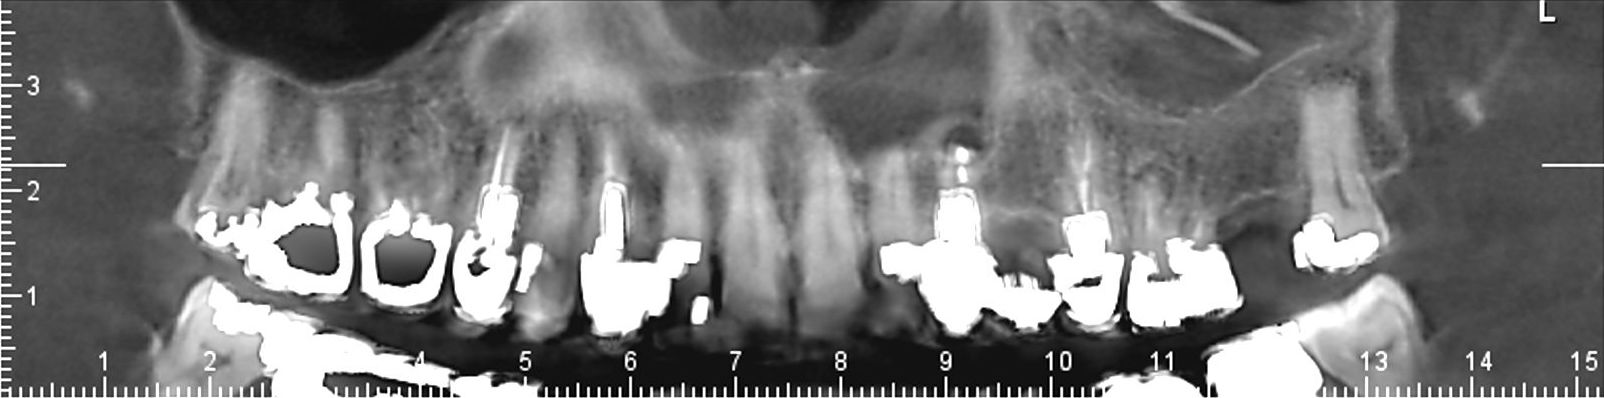

Images de panoramiques dentaire:

Le cone beam est une nouvelle technique de radiographie numérisée situé entre le panoramique dentaire et le scanner, il utilise un faisceau d’irradiation de forme conique d'où son nom. Cet appareil présente notamment l’avantage d’être plus précis que le panoramique dentaire et il possède une résolution similaire, voire supérieure à celle du scanner, avec en plus la possibilité d’une reconstruction numérique en 3D.

Le cone beam utilisé en pathologie dentaire et maxillo-faciale est indiqué pour l’examen des tissus minéralisés (dents, cartilages, os), il permet d’identifier les lésions osseuses, les fractures, les infections, les kystes ou les corps étrangers.

Il est un examen de choix en implantologie.

Le cone beam dentaire est par exemple indiqué dans les pathologies suivantes :

- implants dentaires